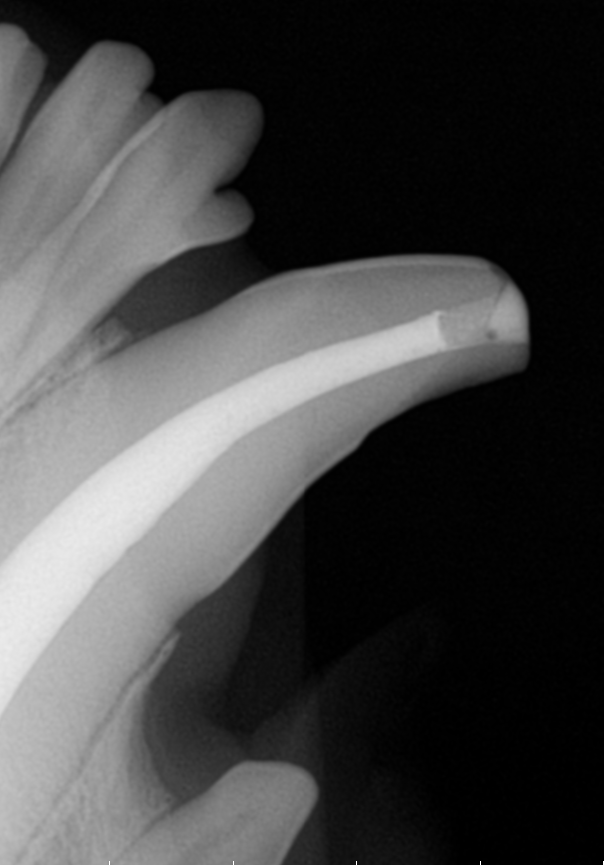

Root Canal Therapy (Endodontics)

We offer Root Canal Therapy for patients that have non-vital or fractured teeth that have pulp exposure. When a pet has a broken or non-vital tooth, it can be really painful and cannot be left or watched.